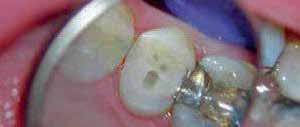

A systemic antibiotic (2g amoxicillin-clavulanic acid, per-orally) was administered to the patients 1 hour prior to the procedure. The patient’s mouth was rinsed with a solution of chlorhexidinedigluconate 0.2% for 2 minutes. After surgical guide printing, the tooth was extracted and the implant placed (IDI implant Implants Di usion International 23/25) following implant placement protocol using a fully guided CAD CAM surgical guide. 14 (fig 3,4,5)

Figure 5: Fully guided implant placement through the surgical guide using spoons. The implant was inserted at the planned position.